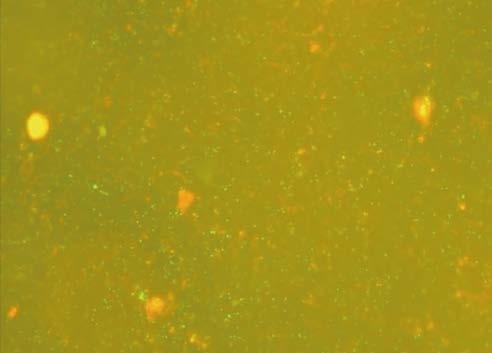

Similarly to MIC results, superior effectiveness of linden and heather honeys was observed in the assessment of antibiofilm activity. Linden honey led to a reduction in biofilm by 54–67% after 4 hours of exposure, while heather honey showed a reduction at the level of 45–58%. Buckwheat and multifloral honeys exhibited much weaker antibiofilm effects, with their biofilm reduction below 20% (Figure 1).

A C Control B D

Figure 1. Antibiofilm activity of Polish honeys against Pseudomonas aeruginosa after 4 hours of exposure. A) Linden honey; B) Heather honey; C) Buckwheat honey; D) Multifloral honey

was conducted for only 4 hours, meaning it was not mature and could be more susceptible to the compounds present in honey. In antibiofilm studies of Portuguese heather honey [27], a different methodology was applied, examining the logarithmic reduction in colony count. A 50% honey concentration led to approximately 50% decrease in the logarithm of colony count.